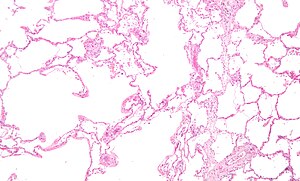

Micrograph of an emphysematous lung; emphysema is a common respiratory disease, strongly associated with smoking. H&E stain.

Asthma, chronic bronchitis, bronchiectasis and chronic obstructive pulmonary disease (COPD) are all obstructive lung diseases characterised by airway obstruction. This limits the amount of air that is able to enter alveoli because of constriction of the bronchial tree, due to inflammation. Obstructive lung diseases are often identified because of symptoms and diagnosed with pulmonary function tests such as spirometry. Many obstructive lung diseases are managed by avoiding triggers (such as dust mites or smoking), with symptom control such as bronchodilators, and with suppression of inflammation (such as through corticosteroids) in severe cases. One common cause of COPD including emphysema, and chronic bronchitis, is tobacco smoking, and common causes of bronchiectasis include severe infections and cystic fibrosis. The definitive cause of asthma is not yet known.[4]